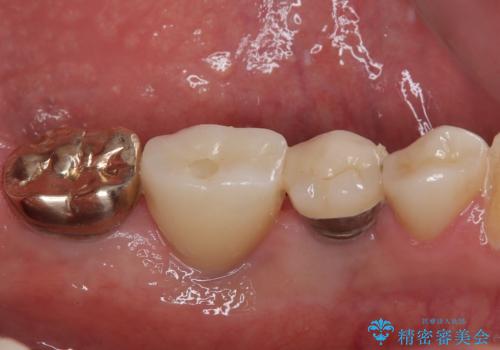

インプラント埋入時に植立具合の安定性を測定したところ、十分な数値が得られたため、速やかに仮歯を装着して咬合回復をさせることができました。

抜歯を含めた外科処置を1回に抑えることができ、あっという間に治療を終えることができました。